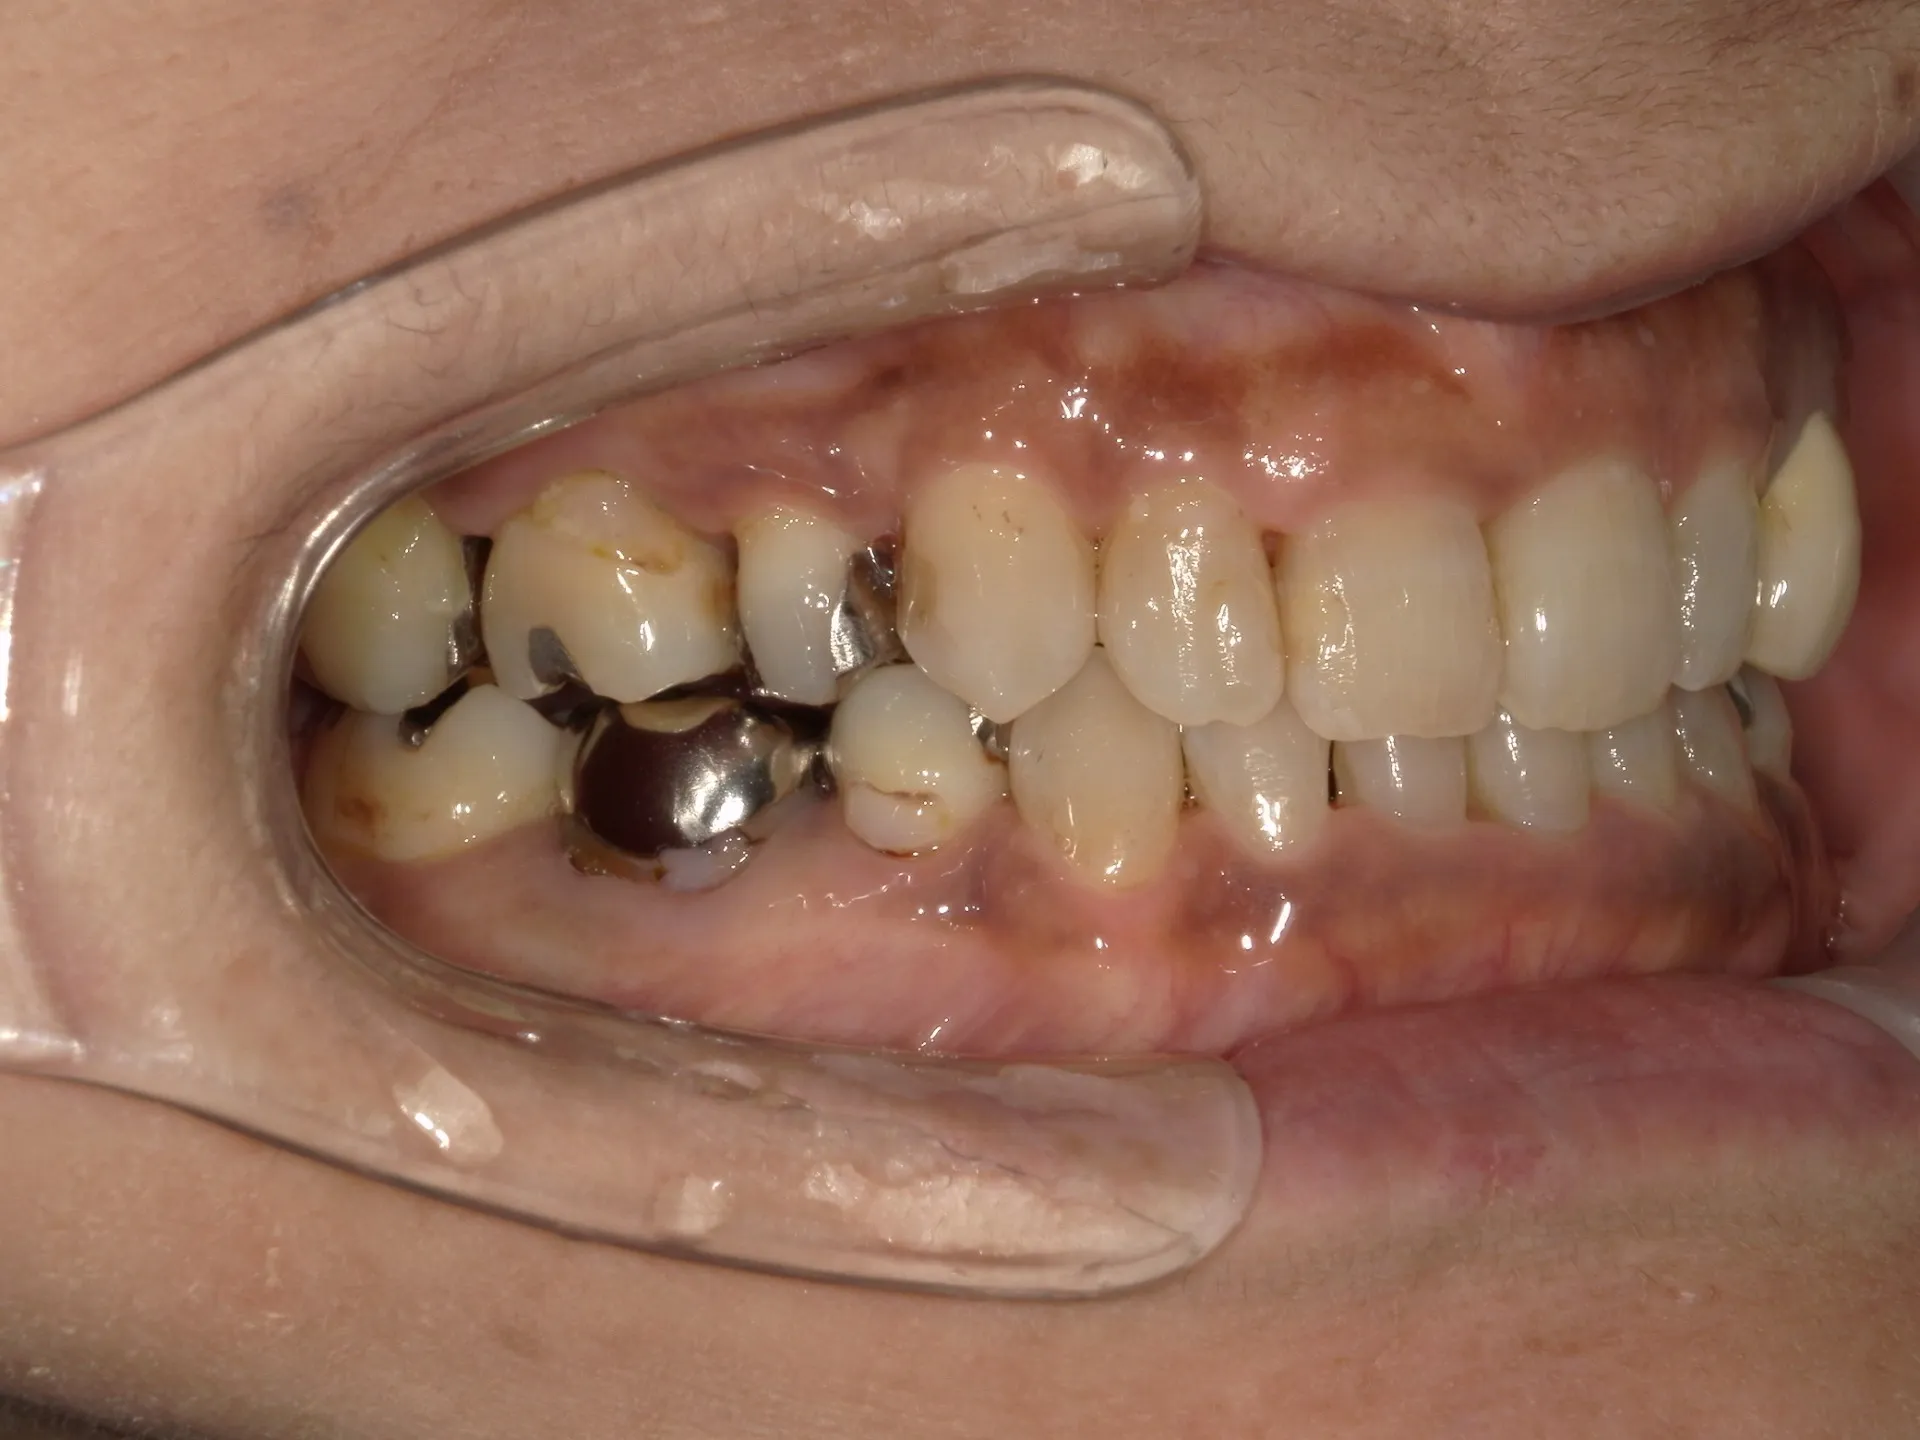

今回は65歳以上でも矯正治療を開始した症例についてご紹介いたします。

しかし、年齢がたとえ定年を迎えたあとであっても十分に矯正が行えて、今後の歯磨きが容易になり、虫歯や歯周病のリスクが減らせて歯を残すことが出来たり、歯並びが良くなったことでモチベーションも上がるなどの矯正後のメリットも非常に高いため、健康的な生活を行う上でも矯正治療は行うことをお勧めします。